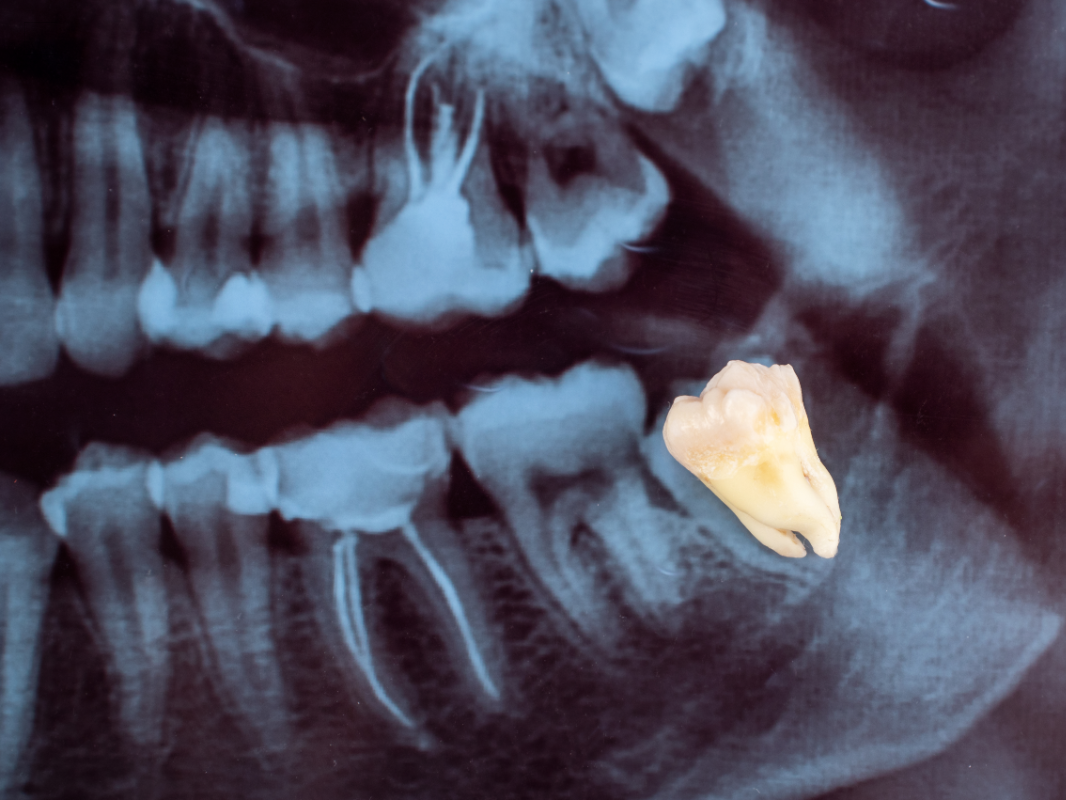

A extração do dente siso é uma cirurgia para remover o terceiro molar, que pode estar visível ou incluso (ainda dentro da gengiva). O procedimento envolve anestesia local. O siso pode ser retirado inteiro ou fragmentado, seguido por limpeza e sutura da área. A recuperação inclui cuidados com alimentação e higiene, e o tempo de recuperação varia conforme a complexidade da cirurgia. Em nosso tratamento você receberá medicamento pré e pós-operatório e orientaremos sobre todo cuidado após o procedimento cirúrgico e completa cicatrização dos tecidos.